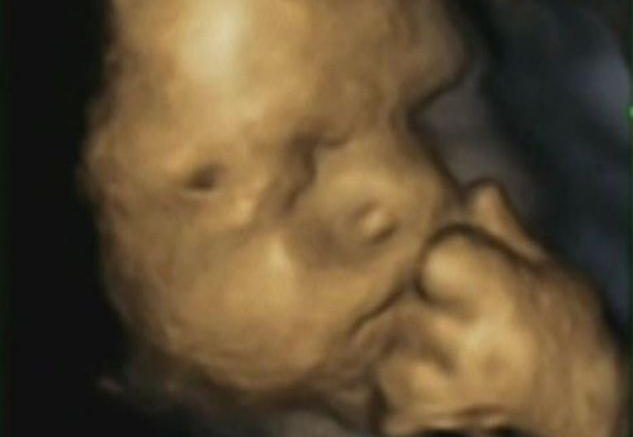

Hasta el momento no se había reparado en el comportamiento del bebé dentro del útero cuando la madre tiene signos de estrés, por eso un equipo de investigadores de las universidades de Durham y Lancaster han decidido estudiarlo y han publicado imágenes de ecografías en 4D para enseñarnos cómo son los gestos del bebé dentro del vientre de una madre estresada.

Se ha hecho un seguimiento del embarazo de 15 bebés entre las semanas 24 y 36 de gestación y se les preguntó a sus madres sobre su nivel de estrés en las últimas semanas.

Los científicos han observado que los bebés de madres estresadas tienden a tocarse la cara más a menudo con su mano izquierda. Cuanto más estrés, más se tocaban los bebés la cara con esa mano.

También han visto que los bebés de madres que sufrían estrés bostezaban abriendo más la boca que los bebés de madres que no lo sufrían, aunque no sabemos exactamente qué les sugiere este hallazgo.